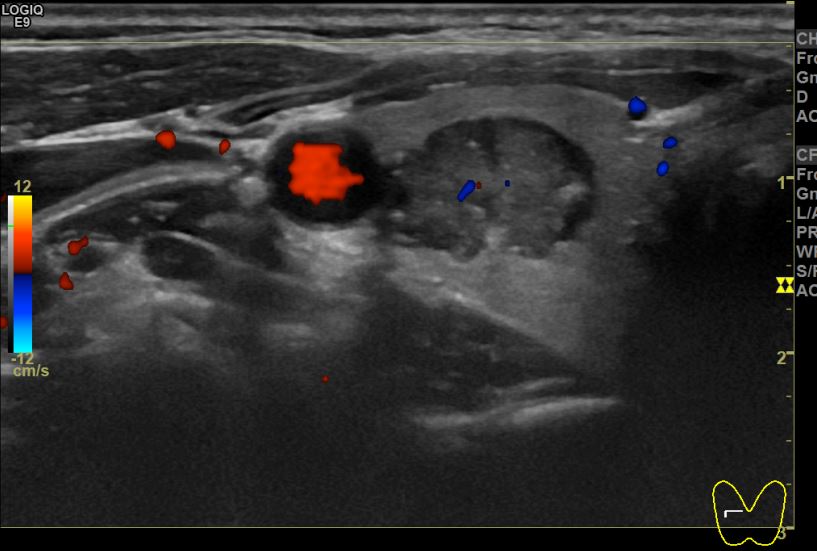

상기환자 외부검사이상소견으로 내원하신 30대 중반 여성분으로 의심스러운 우엽혹 세포검사진행후 갑상선암으로 진단되었습니다